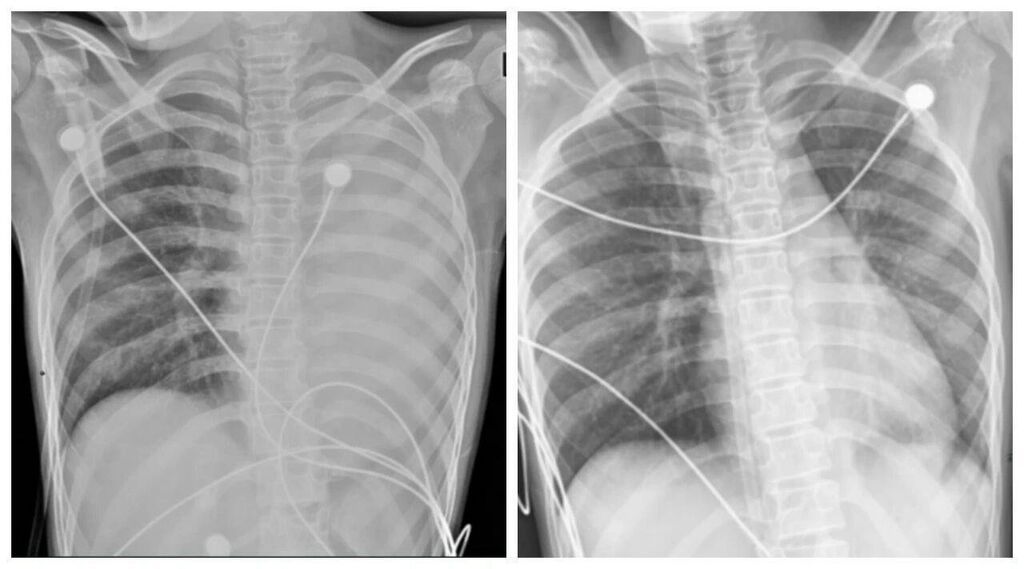

一开始,她只是轻微咳嗽,发热后在外院检查提示肺炎、肺不张,转诊到浙大四院儿科时,笑笑出现呼吸急促、胸闷胸痛,血氧饱和度勉强维持在90%左右,胸片显示左肺已完全呈“白肺”改变,病情急剧恶化。

手术中,支气管镜刚进入气道就发现,笑笑的气道黏膜充血水肿,大量黄白色黏痰不断涌出,左主支气管及各肺段开口已被黏液栓完全堵死。医护团队争分夺秒,用负压吸引、灌洗、钳取等方式清理堵塞物,经过反复操作,终于打通了被堵塞的呼吸通道。

术后第二天,笑笑呼吸困难、胸痛的症状明显好转,病情得到了初步控制。经过精准抗感染、祛痰、抗炎等系列治疗,笑笑逐渐康复,顺利出院。